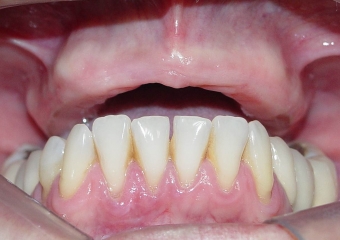

Sorriso final do caso terminado em junho de 2011